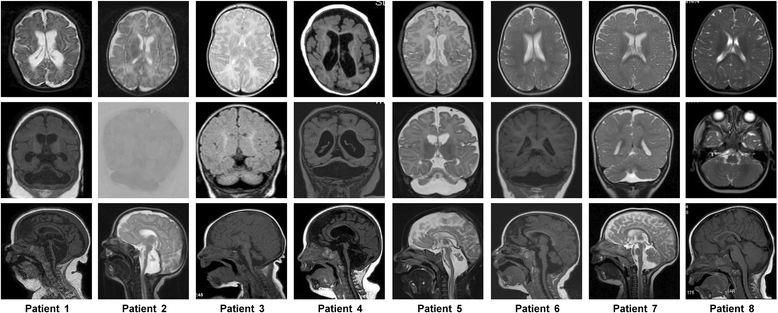

Methods: We identified a CASK alteration in 8 novel unrelated male patients by targeted Sanger sequencing, copy number analysis (MLPA and/or FISH) and array CGH. CASK transcripts were investigated by RT-PCR followed by sequencing. Immunoblotting was used to detect CASK protein in patient-derived cells. The clinical phenotype and natural history of the 8 patients and 28 CASK-mutation positive males reported previously were reviewed and correlated with available molecular data.

Results: CASK alterations include one nonsense mutation, one 5-bp deletion, one mutation of the start codon, and five partial gene deletions and duplications; seven were de novo, including three somatic mosaicisms, and one was familial. In three subjects, specific mRNA junction fragments indicated in tandem duplication of CASK exons disrupting the integrity of the gene. The 5-bp deletion resulted in multiple aberrant CASK mRNAs. In fibroblasts from patients with a CASK loss-of-function mutation, no CASK protein could be detected. Individuals who are mosaic for a severe CASK mutation or carry a hypomorphic mutation still showed detectable amount of protein.

Conclusions: Based on eight novel patients and all CASK-mutation positive males reported previously three phenotypic groups can be distinguished that represent a clinical continuum: (i) MICPCH with severe epileptic encephalopathy caused by hemizygous loss-of-function mutations, (ii) MICPCH associated with inactivating alterations in the mosaic state or a partly penetrant mutation, and (iii) syndromic/nonsyndromic mild to severe ID with or without nystagmus caused by CASK missense and splice mutations that leave the CASK protein intact but likely alter its function or reduce the amount of normal protein. Our findings facilitate focused testing of the CASK gene and interpreting sequence variants identified by next-generation sequencing in cases with a phenotype resembling either of the three groups.